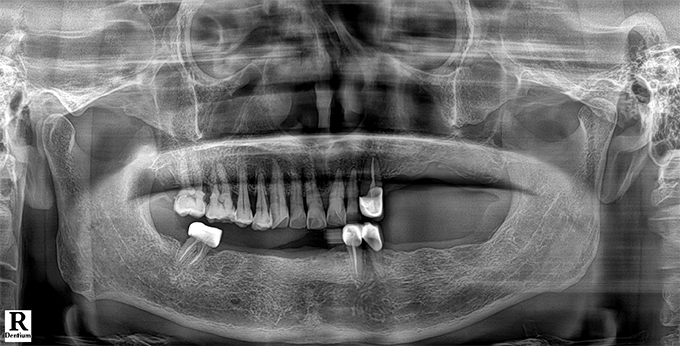

Before & After

임플란트 전후사진

before

2022.10.27

After

2022.11.21

※ 상기 치료전후 사진은 환자의 동의 하에 게재되는 것이며 동일한 촬영각도로 촬영 하였고 치료 기간을 명시하였습니다.

이러한 치료의 결과는 이 환자분에게만 해당되는 것이며 환자의 상태에 따라 똑같은 결과를 얻지 못할 수도 있습니다.

환자분의 상태에 따라 치료 기간, 효과 및 부작용은 상이할 수 있습니다.

치료전후 사진 게재는 의료법 제 23조, 제56조에 의거하여 게재합니다.